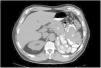

The next day, the patient had no signs of active bleeding and abdominal CT scans, with and without oral contrast, showed the surgical absence of the left kidney. The renal fossa was occupied by a 68×94×56mm tumor that infiltrated the wall of the colon, under the splenic angle, reducing the intestinal lumen. The image suggested invasion into a surrounding segment of the jejunum, as well as a tumor that was retroperitoneal in relation to the suprapancreatic lymph nodes, indicative of metastatic activity, that invaded the lesser curvature of the stomach (Fig. 2). The histopathologic report revealed the presence of ulcerated, metastatic clear cell renal cell carcinoma, with the presence of newly formed vessels and an inflammatory infiltrate with a predominance of macrophages.